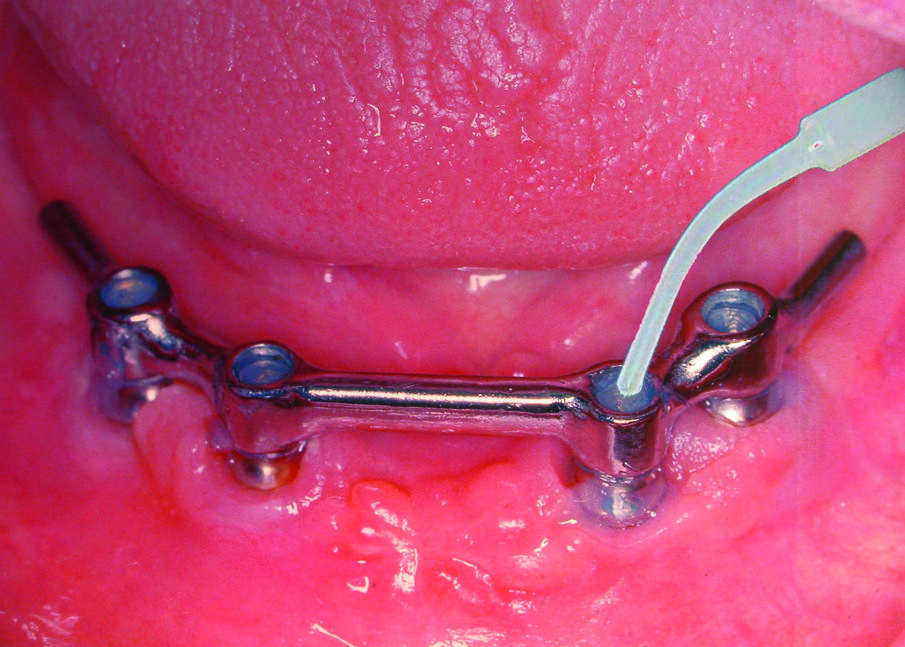

Fig. 2: Recesses underneath a mandibular prosthesis supported by an implant bar.

Fig. 4: Filling of an implant bar construction in the mandible with GapSeal.

GapSeal is supplied in sterile blister packs containing ten ampoules of 0.06 ml each and an applicator, ensuring sterility even for surgery (Fig. 3). The applicator can be resterilised for reuse. Hollow spaces should be sealed as soon as possible—preferably at the time of restoration. After inserting the GapSeal ampoule into the applicator and removing the cap, the clinician applies GapSeal directly by simply turning the wheel. The space is filled with a surplus of material so that there are no air pockets. The ampoules are designed for single use. In the situation that the hollow spaces cannot be loaded with the sealing material until later, it is recommended to clean them thoroughly beforehand with hydrogen peroxide and alcohol. In the case of a prosthesis with retaining screws, the dentist should re-apply GapSeal at recall appointments (Fig. 4).